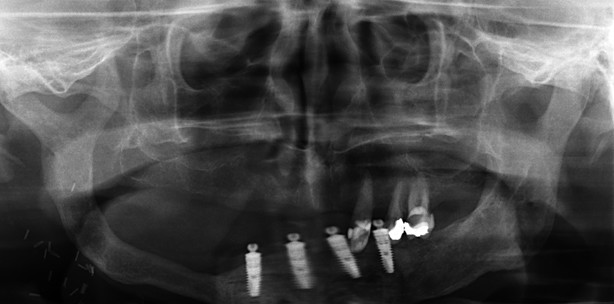

Der präfabrizierte Radialislappen wurde bei fünf Patienten im Rahmen von Sekundärrekonstruktionen großer tumorbedingter Unterkiefer- und Gesichtsdefekte zwischen 2003 und 2006 angewandt. Alle Patienten wurden postoperativ adjuvant bestrahlt und die Primärrekonstruktionen sowohl mikrovaskulärer (2x Fibulatransplantation) als auch die freien Transplantationen (3x freier Beckenkamm – Fibula aufgrund von Gefäßvariation nicht möglich) verliefen erfolglos. Die Defektgröße lag zwischen 7 cm und 11cm (zwei Defekte vom Kieferwinkel bis zur Mittellinie, ein Defekt inter-foraminal, zwei Defekte am Ramus mandibulae betreffend). Eine detaillierte Darstellung findet sich in Tabelle 1. Dabei finden sich die Lokalisationen in Form der schwarzen Balken auf den Röntgenbildern wieder. Weiterhin sind Patientenalter und die Defektgröße angegeben.

Nach der Rekonstruktion des Unterkiefers erhielten die Patienten zunächst die regulären drei- bis sechs- monatigen Nachuntersuchungen im Hinblick auf ein Tumorrezidiv. Bei einem der fünf Patienten konnte im Verlauf eine dentale Rehabilitation durchgeführt werden (Abb. 6). Radiologische Kontrollen mittels Orthopantomogramm wurden präoperativ, unmittelbar postoperativ, nach sechs Monaten, ein und zwei Jahre postoperativ durchgeführt.

Der Nachuntersuchungszeitraum betrug zwischen 8 und 48 Monaten (Mittelwert: 20 Monate). Eine ästhetisch zufriedenstellende Deckung der mandibulären Defekte konnte erreicht werden (Abb. 7). Die knöcherne Rekonstruktion führte zu einer guten und stabilen Korrektur der Asymmetrie des unteren Gesichtsdrittels mit verbessertem ästhetischen Resultat. Die extraorale Hautstruktur war befriedigend. Die Mundöffnung war vergleichbar derjenigen vor der sekundären Rekonstruktion und lag zwischen 2cm und 3,5cm. In einem Fall konnten dentale Implantate im Bereich der ursprünglichen Mandibula inseriert werden (Abb. 6).

Im Rahmen der klinischen Nachsorge konnten weder Frakturen der Knochentransplantate selbst noch Frakturen im Kontaktbereich von Transplantat und ursprünglicher Mandibula beobachtet werden. Zu Schraubenlockerung oder extraoraler Exposition von Osteosynthesematerial kam es in keinem der Fälle. Die Rekonstruktionen unter Verwendung eines präfabrizierten Radialislappens waren nach Entfernung des Osteosynthesematerials nach sechs bis neun Monaten biomechanisch stabil. Es zeigte sich eine suffiziente Einheilung der Transplantate. Allerdings war in einem Fall eine zusätzliche Transplantation von freier Beckenspongiosa bei der Materialentfernung notwendig. Die Spongiosa wurde in einen Spalt zwischen mandibulärem Stumpf und Spongiosa des präfabrizierten Radialislappens eingebracht. Der Transplantatknochen zeigte im Rahmen der Materialentfernung mit einer deutlichen Blutung aus dem Knochen Zeichen der Revaskularisation. Zwei radiologische Befunde sind besonders erwähnenswert. Unmittelbar nach der Transplantation war keinerlei Radioopazität im Vergleich zu dem Unterkieferknochen feststellbar. Unter funktioneller Belastung nach der Materialentfernung zeigte sich im Rahmen der Nachkontrollen eine erhebliche Steigerung der Radioopazität als Indikator einer zunehmenden Mineralisierung und Knochenremodeling des Transplantates. Eine externe kompakte Knochenlamelle konnte ein Jahr nach der Transplantation des präfabrizierten Radialislappens nachgewiesen werden und wurde als Zeichen der Transformation des spongiösen Knochentransplantates in normale knöcherne Strukturen gewertet. Postoperative Röntgenaufnahmen (OPG) zeigten eine Abnahme der vertikalen Knochenhöhe von 18 mm auf 14mm während der Nachbeobachtungszeit (12 bis 17 Monate). Danach konnten keine weiteren Abnahmen der Knochenhöhe beobachtet werden.